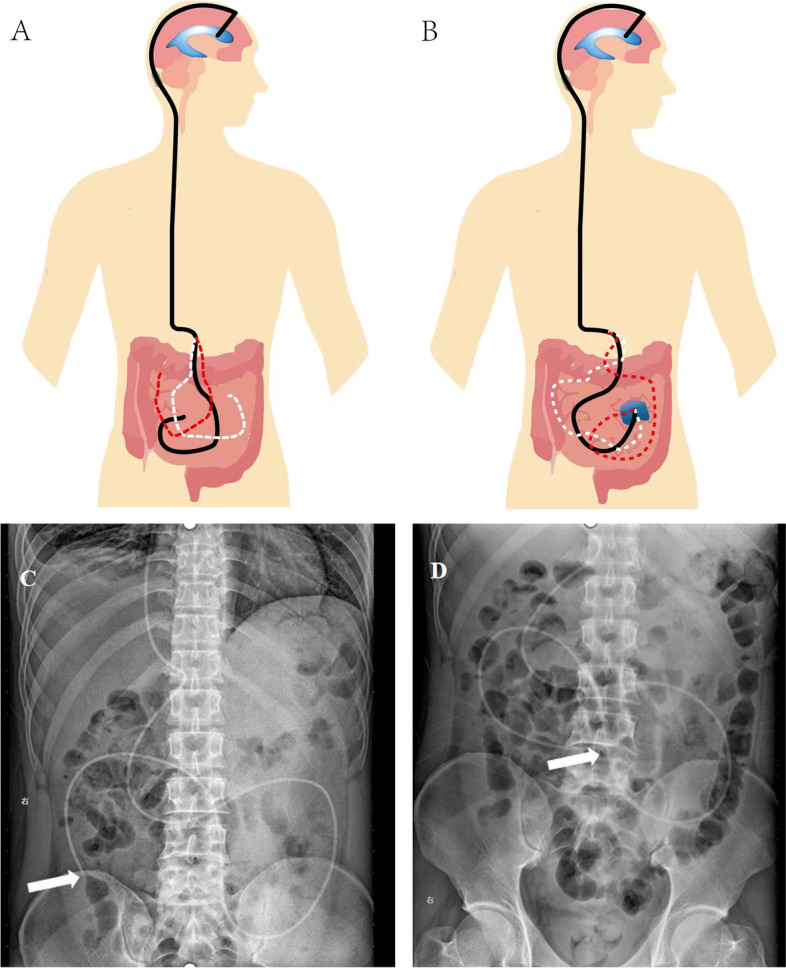

Background: Many complications may occur after placement of the ventriculoperitoneal shunt (VP shunt) for hydrocephalus, and delayed shunt insufficiency (DSI) is among the most common. It is often caused by abdominal adhesions, which increases the difficulty of diagnosis. This study aimed to explore the clinical value of dynamic plain abdominal radiography (DPAR) as a simple diagnostic method for patients with DSI due to terminal adhesion of the peritoneal shunt after VP surgery.

Methods: A total of 30 patients with high suspicion of DSI due to abdominal adhesions after VP surgery were included. DPAR was used for prospective assessment. The interval between the first and second PAR was 4-6 h before surgery. If two plain abdominal radiography at different times indicated that the end of the shunt tube in the abdominal segment was fixed, it was diagnosed as DSI due to adhesion of the shunt tube at the abdominal end. The peritoneal end of the shunt tube was surgically repositioned. Postoperative DPAR was repeated to evaluate the distance of the shunt outlet within the abdominal segment.

Results: All cases showed clinical symptoms or imaging findings of shunt insufficiency. The diagnostic accuracy of DPAR was 96.67% (29/30). The end of the shunt tube in the abdominal segment of the preoperative group was fixed with abdominal plain film twice with a mean difference of 1.74 ± 1.18 cm. The mean postoperative change in the position of the end of the shunt tube in the abdominal section was 9.36 ± 2.64 cm, showing a significant difference compared with the preoperative group (P < 0.001). The mean postoperative EVANs index (0.37 ± 0.08) was significantly lower than the preoperative (0.42 ± 0.08) (P = 0.007), Glasgow coma scale score (12.8 ± 2.69) was higher than the mean preoperative score (11.36 ± 2.43) (P = 0.013).

Conclusion: DPAR is a simple and effective method for the diagnosis of shunt insufficiency caused by delayed abdominal end adhesion after VP shunt.